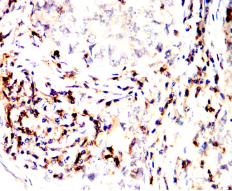

CD45R Mouse Monoclonal antibody[1A5G6]

IHC    1/200 - 1/1000